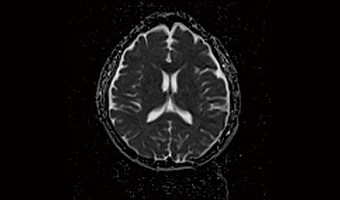

Application Images

Brain SWI, capable of achieving 4-8x acceleration.